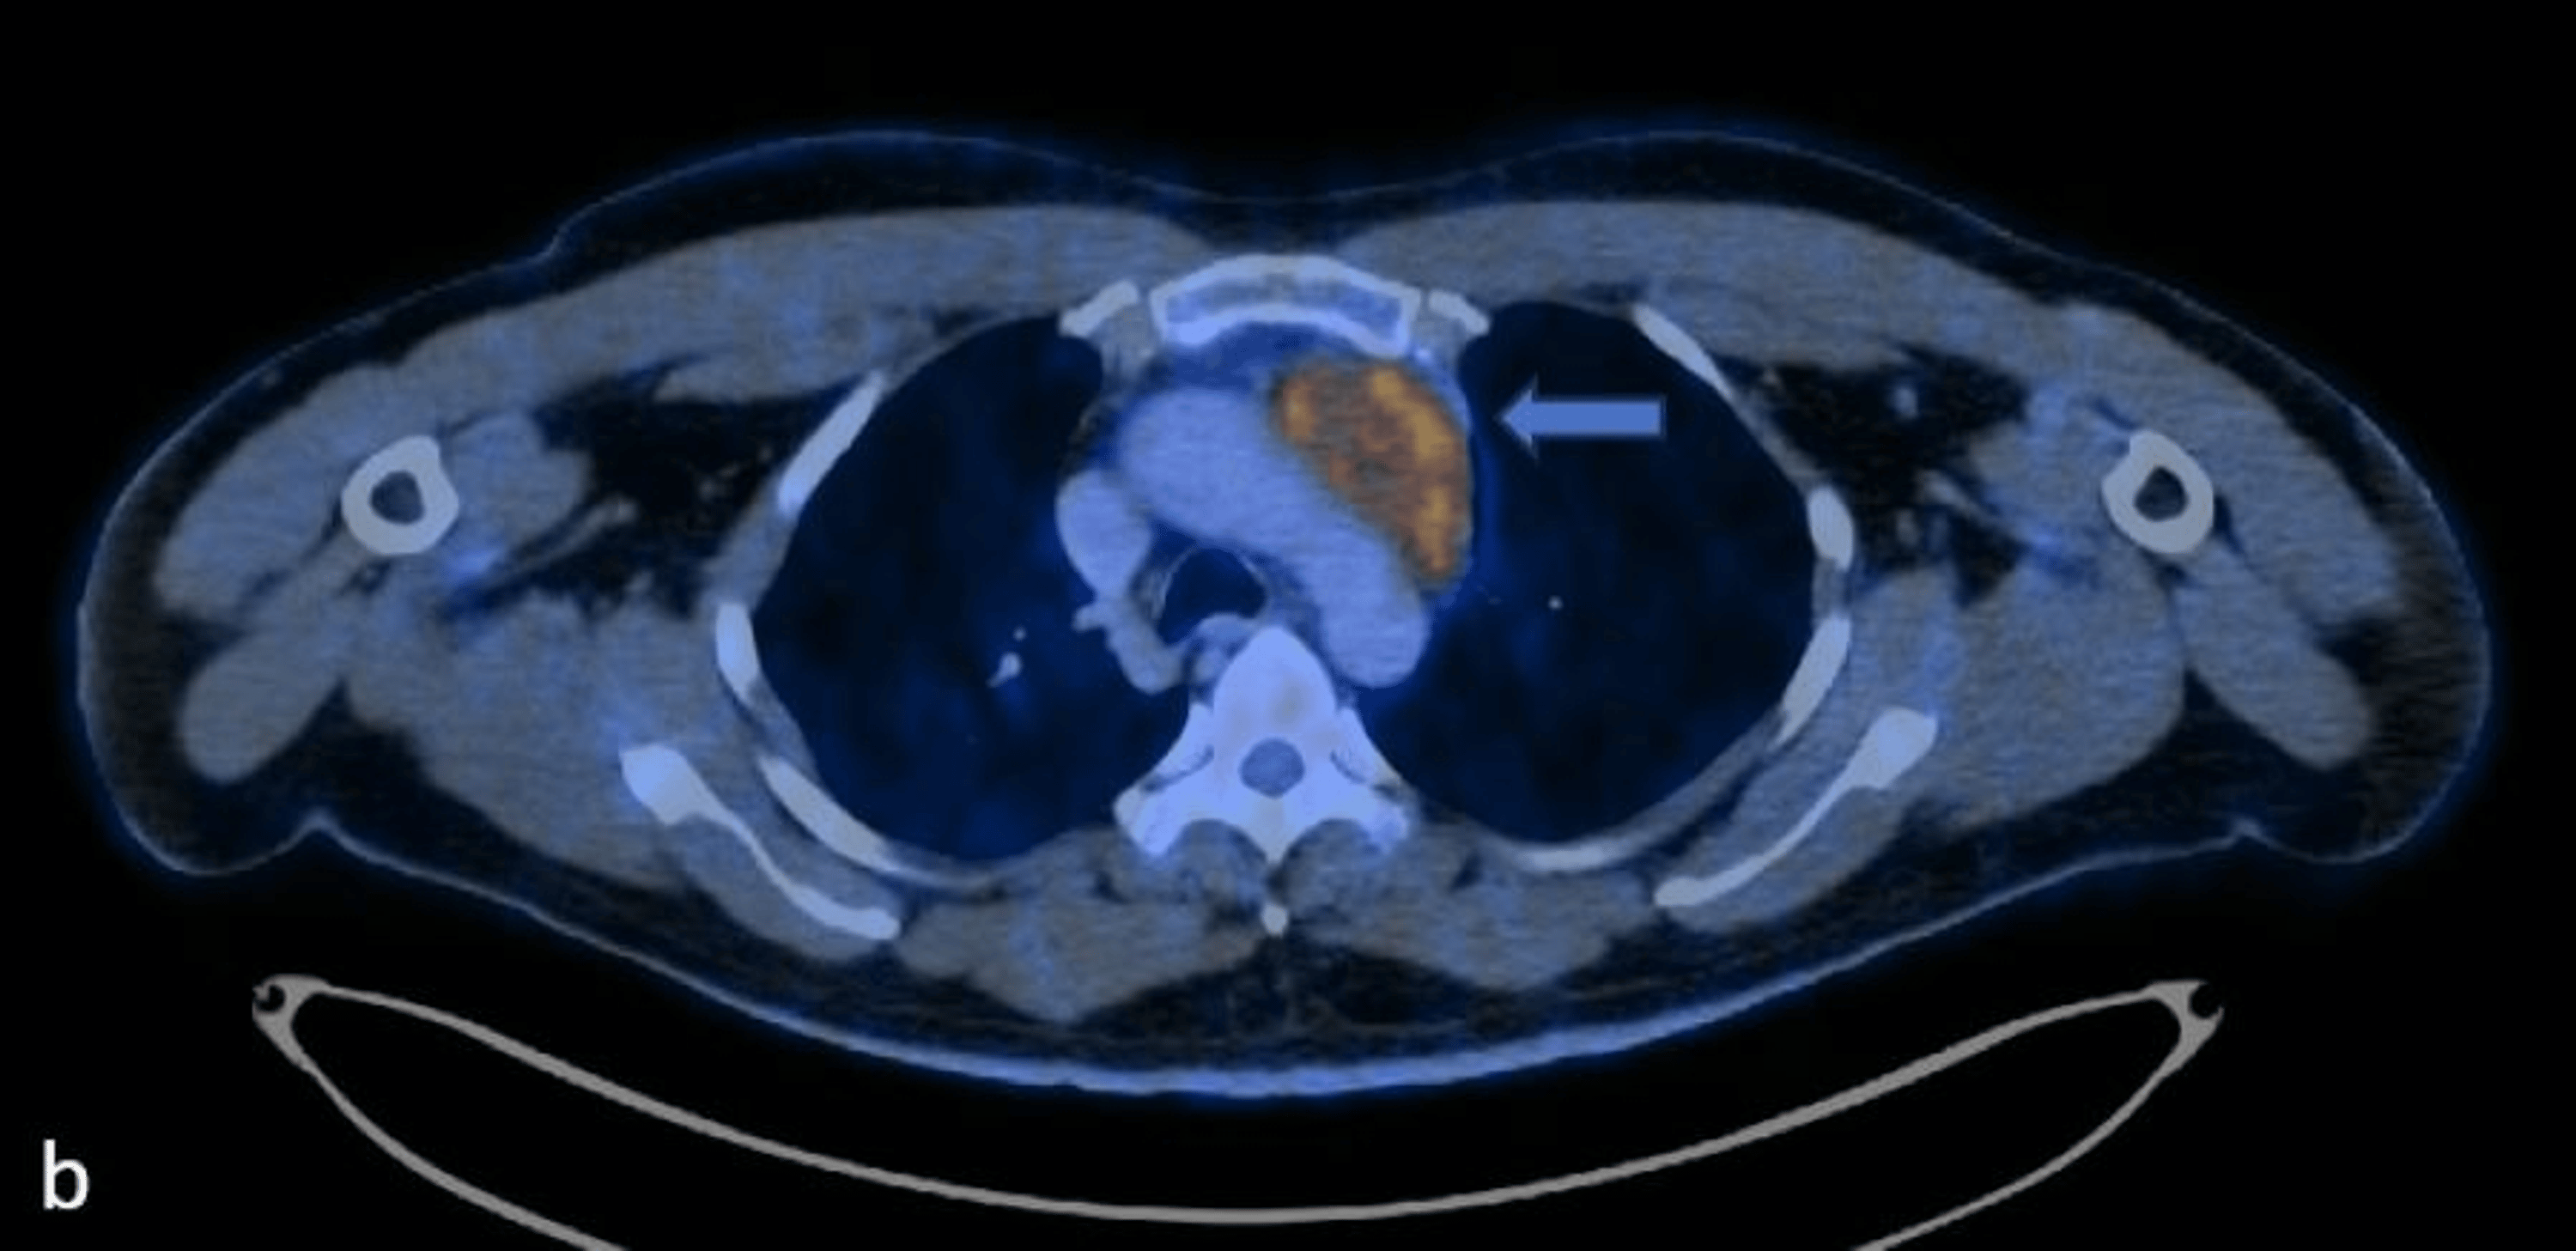

Cancers Free FullText Thymic Lymphoepithelial Carcinoma Associated Thymic Lymphoepithelial Carcinoma Thymic lymphoepithelial carcinoma (tlec) is a primary thymic carcinoma that accounts for about 14% of all thymic epithelial tumors and is classified into. In the who 2021 classification, thymic carcinoma includes the following new subtypes (): Thymic epithelial tumors (tets) are rare tumors, including thymoma, thymic carcinoma, and thymic neuroendocrine tumors. (1) micronodular thymic carcinoma with lymphoid hyperplasia (fig. The. Thymic Lymphoepithelial Carcinoma.

Figure 1 from Thymic Lymphoepithelial Carcinoma Associated with Epstein Thymic Lymphoepithelial Carcinoma (1) micronodular thymic carcinoma with lymphoid hyperplasia (fig. Thymic lymphoepithelial carcinoma (tlec) is a primary thymic carcinoma that accounts for about 14% of all thymic epithelial. Thymic epithelial tumors (tets) are rare tumors, including thymoma, thymic carcinoma, and thymic neuroendocrine tumors. In the who 2021 classification, thymic carcinoma includes the following new subtypes (): The recognition of clinical, radiologic, and.. Thymic Lymphoepithelial Carcinoma.

Cancers Free FullText Thymic Lymphoepithelial Carcinoma Associated Thymic Lymphoepithelial Carcinoma The recognition of clinical, radiologic, and. In the who 2021 classification, thymic carcinoma includes the following new subtypes (): Thymic lymphoepithelial carcinoma (tlec) is a primary thymic carcinoma that accounts for about 14% of all thymic epithelial tumors and is classified into. (1) micronodular thymic carcinoma with lymphoid hyperplasia (fig. Thymic lymphoepithelial carcinoma (tlec) is a primary thymic carcinoma that. Thymic Lymphoepithelial Carcinoma.